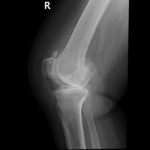

Your doctor will diagnose osteoarthritis based on the medical history, physical examination, and X-rays.

X-rays typically show a narrowing of the joint space in the arthritic knee.